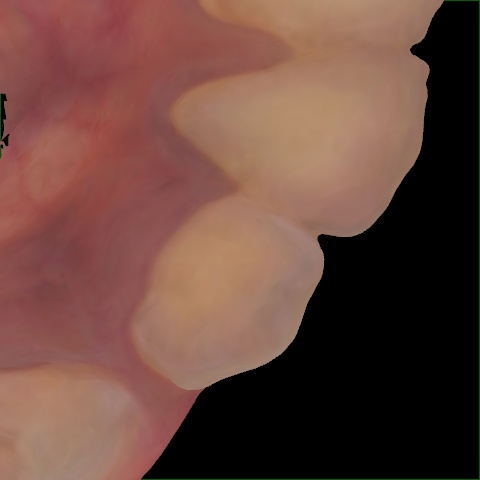

NHD25470

Annotated as "Good"

Original Image Rendering Image